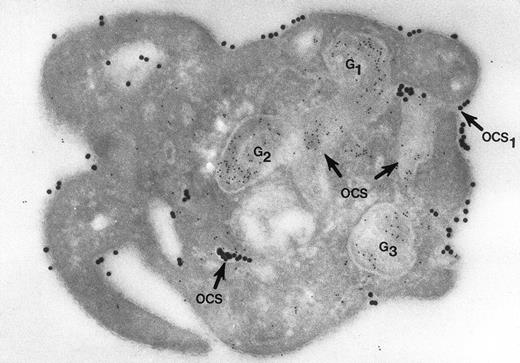

Nor would Morgenstern have made the comment that fusion of membranes of secretory organelles with membranes of the OCS has never been shown. The reports from our laboratory that he cited, and others,18 answer this concern quite well. In one of the experiments, platelets in suspension were combined with 20-nm colloidal gold particles coated with fibrinogen (Fgn/Au), then exposed to thrombin for 1, 3, and 5 minutes without stirring.19 At these intervals the platelets were fixed, frozen, and frozen thin sections prepared. The sections were stained with a polyclonal antifibrinogen antibody and then staph protein A bound to 10-nm gold particles. Thrombin stimulated uptake of 20 nm Fgn/Au gold particles into OCS channels and their transfer to α granules in the process of discharge into the OCS (Fig 1). Protein A 10-nm gold particles demonstrated fibrinogen in nonlabilized α granules and those in the process of discharge into the OCS. The work showed that the OCS was truly a final common pathway; hence, the name of the article.19

Cryosection of blood platelet from a washed cell suspension incubated with 18- to 20-nm colloidal gold particles coated with Fgn/Au for 5 minutes, then exposed to 1 U/mL of thrombin for 60 seconds. The Fgn/Au particles bind to the cell surface and penetrate into peripheral channels of the OCS. After fixation, freezing, and cryotomy, the frozen thin section was stained with a polyclonal antifibrinogen antibody and protein A bound to 5-nm gold particles. Immunogold beads detecting endogenous fibrinogen are concentrated in intact granules (G3) and in granules (G1, G2) in the process of discharging their contents into channels of the OCS. Some of the Fgn/Au particles entering from the outside are mixed with the immunogold beads in the same OCS channels (OCS) communicating with the exterior surface. Original magnification ×60,000. (Reprinted with permission.18)